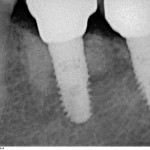

Прицельный радиовизиографический снимок можно сделать в любой из наших клиник. В отличие от обычных прицельных рентгенограмм зубов, доза лучевой нагрузки при проведении подобного исследования в несколько раз ниже, поэтому таких снимков можно сделать очень много. Например, по существующим стандартам, терапевт стоматолог может сделать до десяти снимком зуба в процессе эндодонтического лечения — и это, разумеется, необходимо для качественного лечения каналов зубов.

В хирургической практике я использую прицельные снимки как для первичной диагностики: например, чтобы быстро понять локализацию ретинированного зуба мудрости и его отношение к окружающим структурам, либо для интра- и послеоперационного контроля результатов имплантологического лечения. А наличие цифровой базы радиовизиографических снимков позволяет понять, как ведет себя протез на импланте в течение длительного времени: